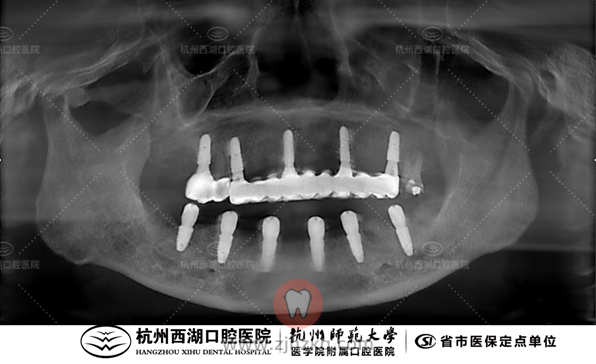

术后CBCT照如下

种植团队采用All-on-6即刻修复技术,为王阿姨植入6颗种植体,即日戴牙完成半口修复。

手术时间:10:00—10:30